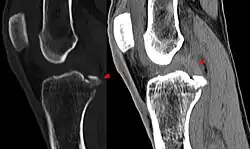

Procédés d'imagerie

Le diagnostic peut être confirmé par imagerie (IRM). Mais il faut noter que l'interprétation de l'IRM seule pour le diagnostic de rupture de LC conduit à 20 % de faux diagnostics. Cela dépend des images de coupe et de la position appropriée du genou pendant l'IRM. Le radiologue doit connaître avec précision les circonstances qui ont conduit à la blessure, et avoir aussi une bonne expérience de l'étude d'une articulation blessée, pour éviter les faux diagnostics. Pour comparer avec l'IRM, le taux d'erreur du test de Lachman, bien plus simple à accomplir, n'est que de 10 %[108],[109],[110],[111]. L'IRM est donc généralement moins sensible et moins spécifique que l'examen clinique par un orthopédiste qualifié[112]. Le résultat de l'IRM n'a que relativement rarement une influence sur la formulation finale du diagnostic[113] et ne devrait pas servir de remplacement pour une anamnèse soigneuse et la palpation[114]. Plusieurs études arrivent à la conclusion que l'IRM n'a de sens que pour des blessures complexes difficiles à expliquer, et là, pour éviter de poser un diagnostic négatif[115],[116],[117].

Les radios n'apportent aucune contribution immédiate au diagnostic de rupture de LC. Les deux LC sont invisibles à la radio, déchirés ou non. La seule utilité de la radio ne peut servir qu'au diagnostic des complications osseuses possibles.

Arthroscopie diagnostique

La sécurité diagnostique la meilleure est obtenue par arthroscopie diagnostique. Ce procédé représente l'étalon-or pour le diagnostic de la rupture de LC. Ce procédé relève d'une chirurgie invasive au minimum, mais comporte certains risques, comme toute intervention chirurgicale dans le genou du patient[118]. Comme cependant le traitement chirurgical d'une rupture de LC sera conduit par chirurgie arthroscopique, il est possible d'enchaîner celle-ci immédiatement après l'arthroscopie diagnostique, par la résection partielle du ligament (pour une déchirure) ou la reconstruction en cas d'arrachement. Avec l'accroissement de la facilité de l'IRM, le nombre d'arthroscopies purement diagnostiques a nettement diminué ces dernières années[119],[120]. L'arthroscopie diagnostique est quand même utilisée comme précédemment comme procédé de choix pour une compréhension certaine du diagnostic de rupture de LC, en cas d'examen clinique confus et d'IRM difficile à interpréter[118].